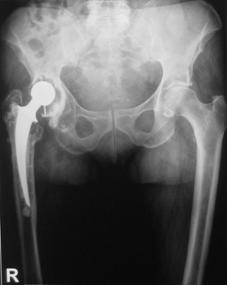

In aceasta lucrare au fost inclusi 35 pacienti, ce au suferit interventii de revizie a componentei femurale, in total efectuandu-se 38 de revizii. Din cei 35 de pacienti 13 au fost de sex feminin si 22 de sex masculin. Din figura nr. 2.2.1 reiese faptul ca 23 de interventii au fost realizate pentru revizia protezei soldului drept si 15 pentru revizia componentei femurale a soldului stang, existand o predominenta a interventiilor la nivelul soldului drept (12) in cazul sexului feminin

Fig. Nr. 2.2.1. - Repartitia pe sexe si lateralitate a interventiilor de revizie.